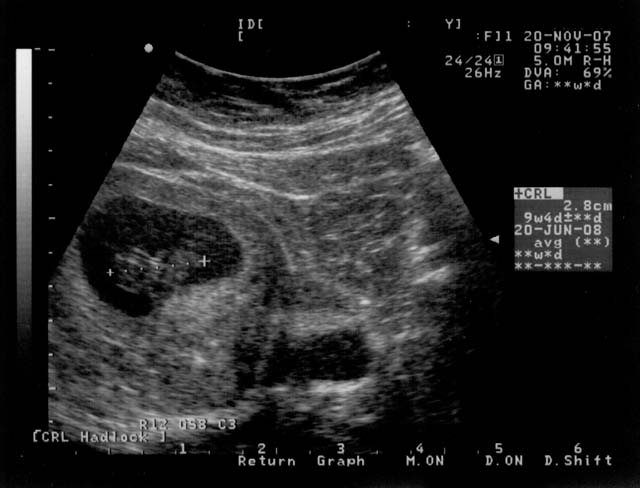

I put a entry into my personal blog last month, but I figured

it was time for another family message. For starters, please

meet peanut:

This picture is a couple weeks old, but it gives you the general idea.

Yes, it has happened! Megan and I are going to have a baby. Please

don't ask whether it will be a girl or a boy, we are planning to find

out, but not until late February. Megan named it peanut because it

was about that size in the ultrasound. As you can see from the

counter, we will meet peanut approximately on June 20th, at which

point we will have a name picked out that is more appropriate.